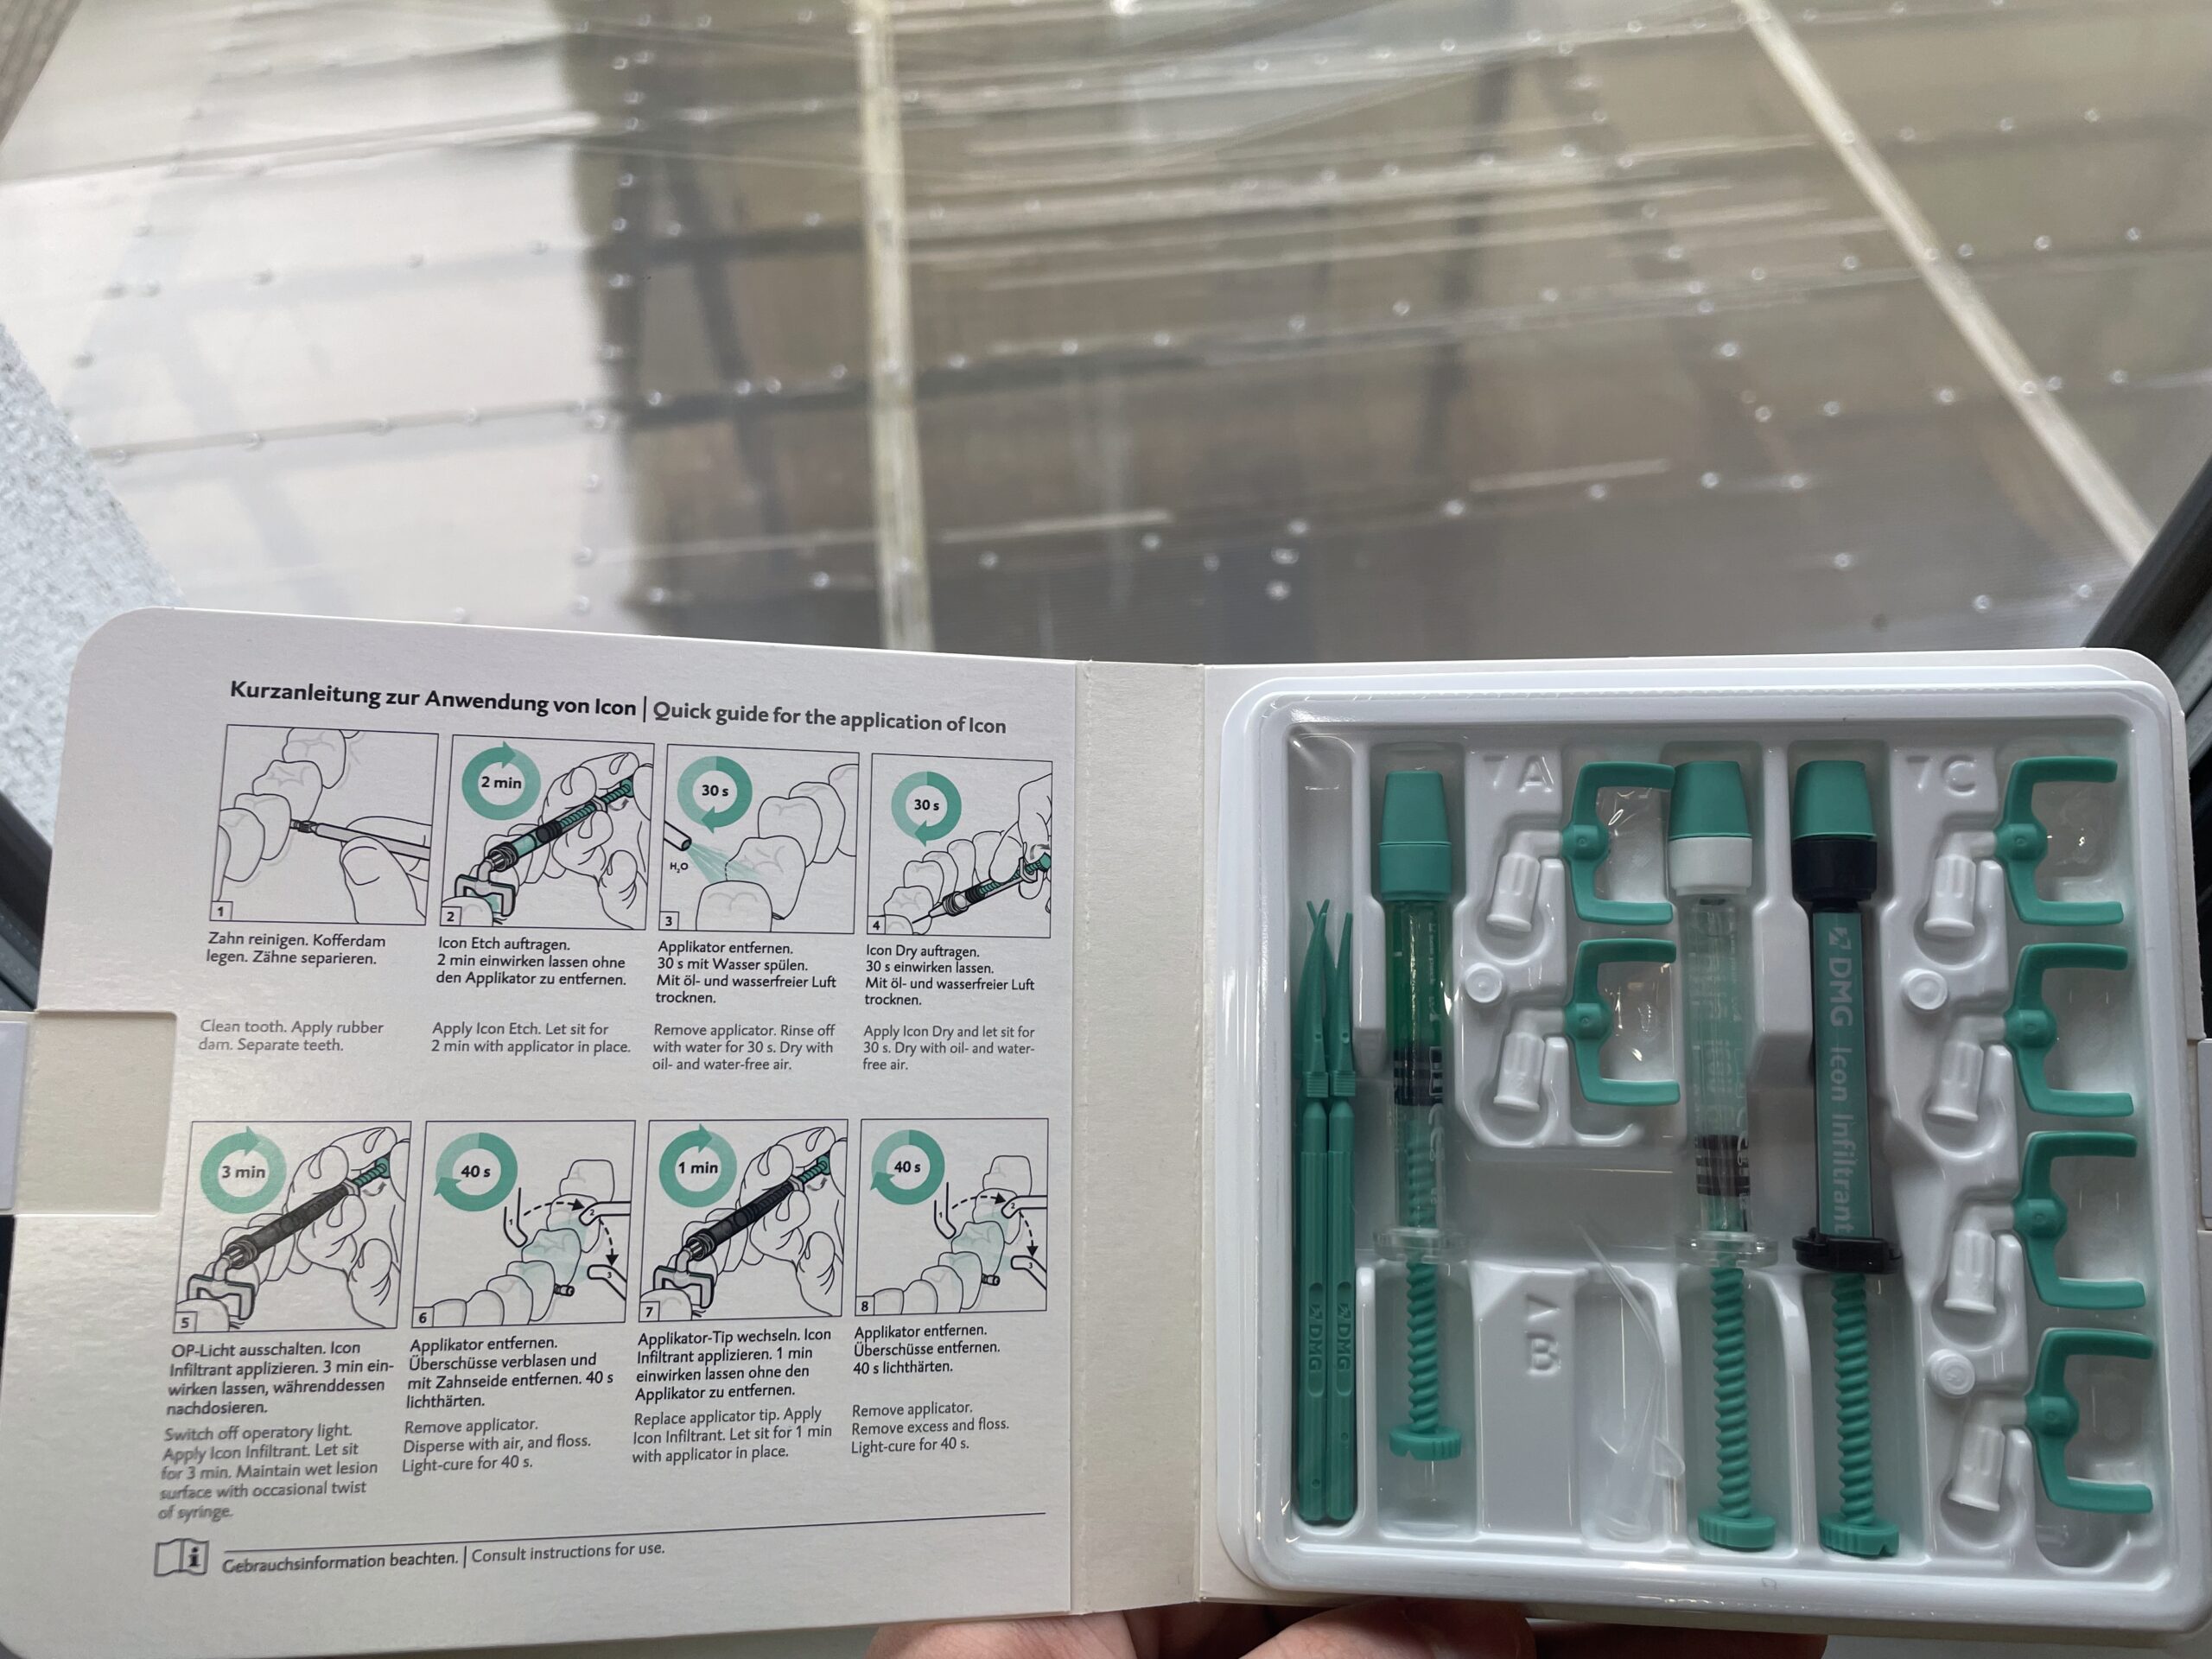

Icon to nowoczesna, mikroinwazyjna metoda leczenia początkowych zmian próchnicowych bez konieczności użycia wierteł. Technika ta polega na infiltracji porowatej struktury zmiany specjalną płynną żywicą, która penetruje i wzmacnia osłabione tkanki. W zależności od lokalizacji zmiany stosuje się dwa warianty produktu:

• Icon Proximal – stosowany do leczenia wczesnych zmian próchnicowych na powierzchniach stycznych, zanim dojdzie do zaawansowanej destrukcji szkliwa.